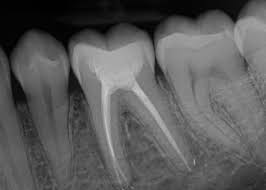

Omogućava preciznu dijagnostiku kanala korena. Brzo se prikazuje, pomaže u planiranju tretmana i povećava sigurnost i uspeh lečenja.

Apex lokator precizno određuje dužinu kanala korena, dok endomotor omogućava bezbednu i efikasnu obradu kanala. Zajedno obezbeđuju tačnost, kraće trajanje tretmana i dugotrajan uspeh lečenja.